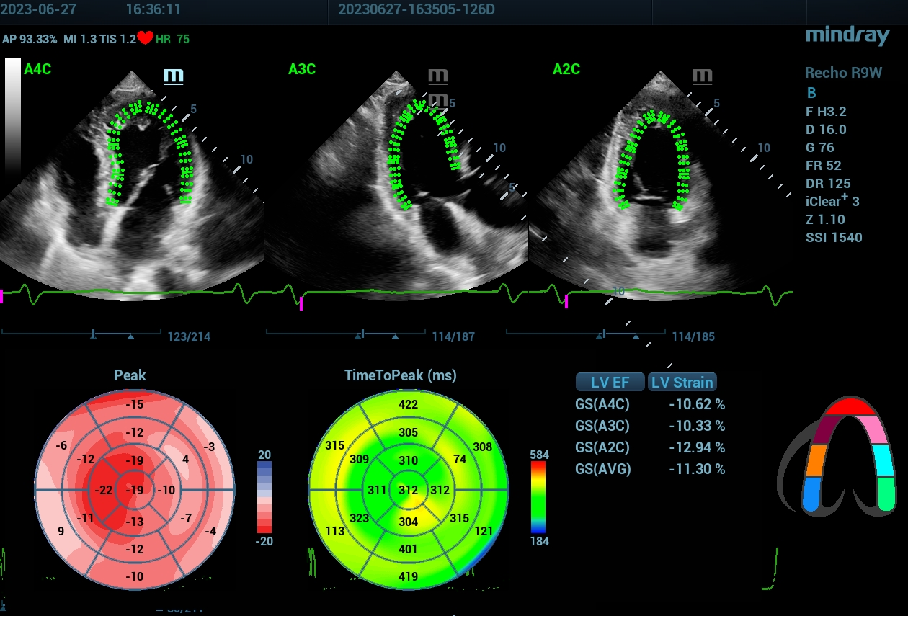

国内首台心脏专用彩超“鲲鹏 Recho R9”,智能左心室应变评估Auto Strain LV